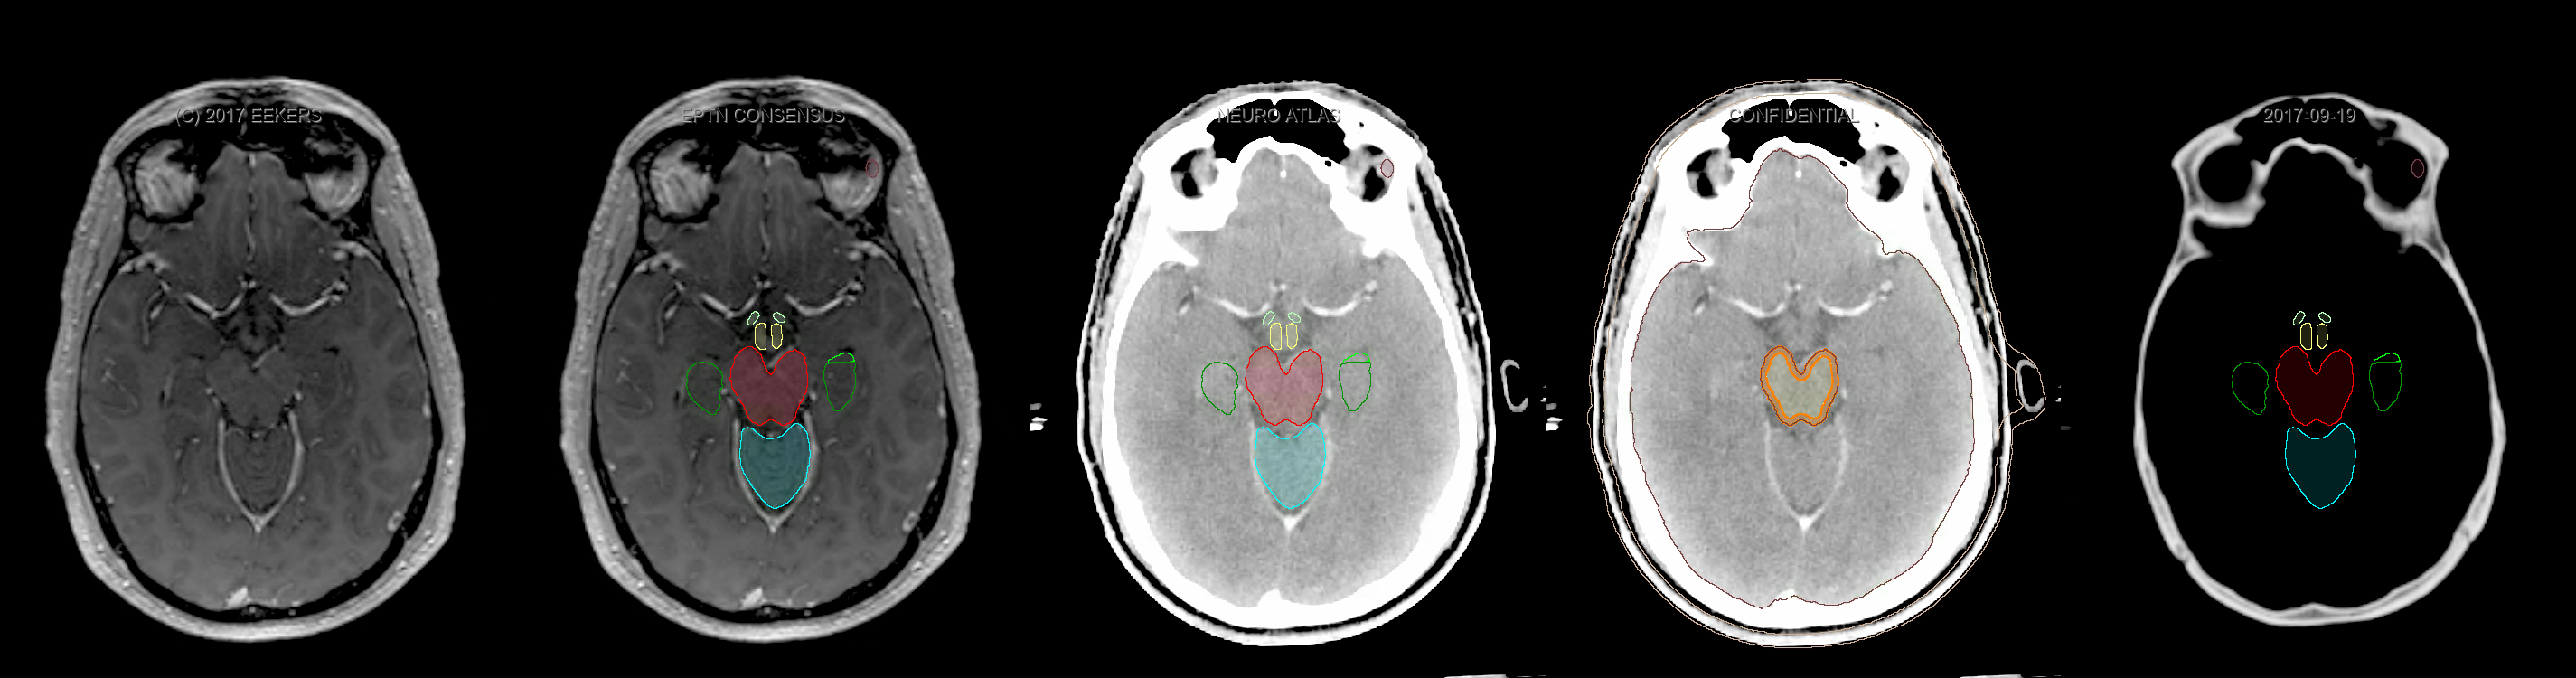

Three-dimensional delineation of the fifteen consensus OARs for neuro-oncology are shown on CT and 3 Tesla (3T) MR images (slice thickness 1 mm with intravenous contrast agent). All are presented in transversal, sagittal and coronal view.

From left to right: MR without structures, MR with structures, CT (WW/WL 120/40) with structures, CT (WW/WL 120/40) with Brain and Brainstem Surface, CT (WW/WL 1500/120)with structures